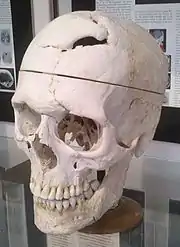

| Burial place | Cypress Lawn Memorial Park, California (skull in Warren Anatomical Museum, Boston) |

In addition, Ratiu et al. noted that the hole in the base of the cranium (created as the tamping iron passed through the sphenoidal sinus into the brain) has a diameter about half that of the iron itself; combining this with the hairline fracture beginning behind the exit region and running down the front of the skull, they concluded that the skull "hinged" open as the iron entered from below, then was pulled closed by the resilience of soft tissues once the iron had exited through the top of the head.

Two daguerreotype portraits of Gage, identified in 2009 and 2010,[note 20] are the only likenesses

Authenticity of the portraits was confirmed by overlaying the inscription on the tamping iron, as seen in the portraits, against that on the actual tamping iron, and matching the subject's injuries to those preserved in the head cast.[W]: 342-43 [L] However, about when, where, and by whom the portraits were taken nothing is known, except that they were created no earlier than January 1850 (when the inscription was added to the tamping iron),[M10]: 644 on different occasions, and are likely by different photographers.[W1]: 8

The portraits support other evidence that Gage's most serious mental changes were temporary .[M9][117] "That [Gage] was any form of vagrant following his injury is belied by these remarkable images", wrote Van Horn et al.[V]: 13 "Although just one picture," Kean commented in reference to the first image discovered, "it exploded the common image of Gage as a dirty, disheveled misfit. This Phineas was proud, well-dressed, and disarmingly handsome." [K]